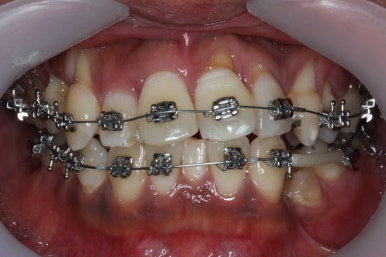

치료 시작 3개월째의 모습입니다.

서서히 가지런해지는 느낌이 드시나요?

화살표를 보면 작은 어금니 하나가 아래로 꺼져있는데, 이 녀석 때문에 애를 먹었네요. 훨씬 치료가 빨리 끝날 수 있었는데 이 치아가 워낙 잘 안움직이는 바람에 2년 개월정도로 치료기간이 많이 걸린 편이었어요.